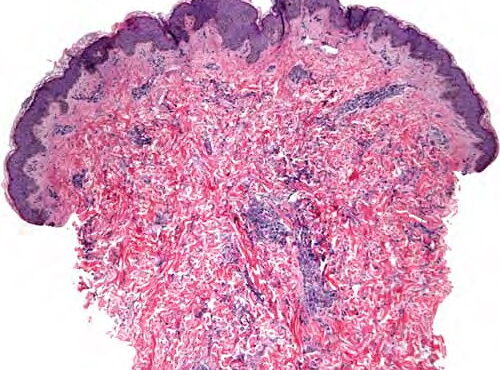

Read MoreInterstitial granulomatous dermatitis = التهاب الجلد الحبيبومي الخلالي